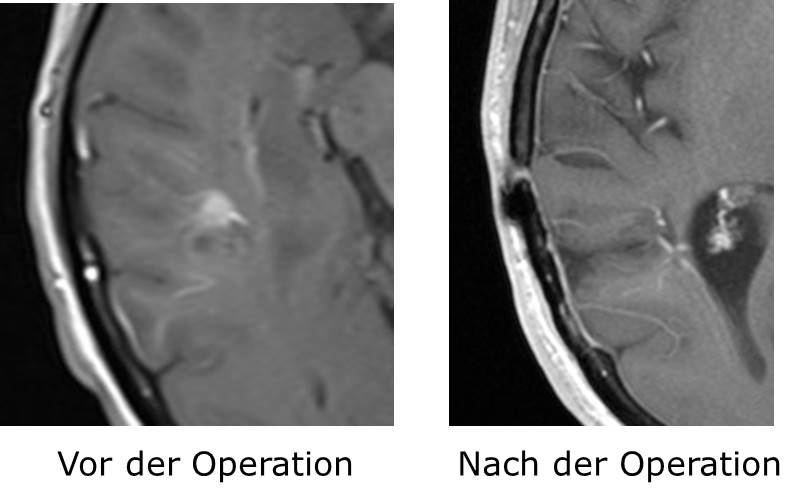

Gefäßfehlbildungen, ob Ausbuchtung eines arteriellen Gefäßes (Aneurysma), arteriovenöse Malformation (kurz: Angiom) oder sogenannte Kavernome werden routinemäßig mikrochirurgisch minimal-invasiv versorgt.

Dazu ist eine spezielle Infrarotausstattung zur Gefäßdarstellung (IR 800) für das Operationsmikroskop als Modul vorhanden.

Die vaskuläre Chirurgie bildet in Sanderbusch einen der Schwerpunkte in der Neurochirurgie

Ein vaskuläres Zentrum mit der Neuroradiologie und Klinik für Neurologie wird etabliert, wo auch endovaskuläre Versorgung von Gefäßbildungen und Rekanalisation der Gefäße  durchgeführt wird. Damit ist die komplette Versorgung der vaskulären Erkrankungen des Gehirns (sowohl operativ als auch endovaskulär) gewährleistet.